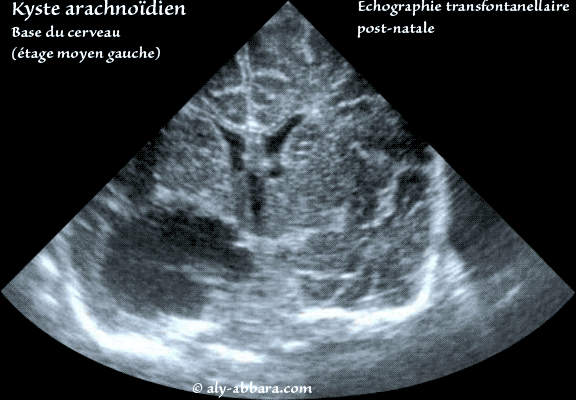

Auto-diaporama d'images échographiques transformationnelles du cerveau d'un nouveau-né montrant la présence d'un volumineux kyste arachnoïdien évoluant au niveau de la base du cerveau, à l'étage moyen avec refoulement du thalamus homolatéral vers le haut. L'ensemble des images montre aussi l'absence de dilatation du système ventriculaire cérébral. Il s'agit d'une anomalie isolée avec par ailleurs une morphologie et un caryotype fœtaux parfaitement normaux. |